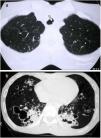

Amyloidosis and light-chain deposition diseaseThe term amyloidosis refers to a heterogeneous group of diseases that have in common the extracellular deposit of insoluble fibrillar proteins with green birefringence on Congo red staining. Amyloidosis can be systemic (80–90% of cases) or localised. Pulmonary involvement occurs in around 50% of cases and has three fundamental patterns of anatomical distribution: tracheobronchial, diffuse interstitial disease, and nodular parenchymal disease. The nodular pulmonary form is almost always a localised disease, with AL amyloid deposits, and is part of the differential diagnosis of diffuse cystic lung diseases. It is associated with collagen diseases, mainly Sjögren’s syndrome, although it also occurs in patients without connective tissue disorders and lymphoproliferative diseases, such as MALT lymphoma.10,16,48–52 CT shows multiple nodules of variable size (from less than 1cm to several centimetres), with smooth or spiculated borders, randomly distributed or predominantly in the lower lung fields, both peribronchovascular and subpleural, and with frequent calcification (up to 50%). Multiple cysts are seen along with the nodules (Fig. 12), which are thin-walled, randomly distributed, and calcified nodules are often seen on the cyst's wall or within it.10,48–51 The possible pathogenesis of the cysts includes airway stenosis due to infiltration of the bronchiolar wall by amyloid and inflammatory cells, with distal dilatation due to a valvular mechanism, rupture of the alveolar walls due to fragility as a result of amyloid deposition, and ischaemia secondary to the deposition of amyloid in the vascular walls.11,13,16,49 The differential diagnosis, especially in patients with Sjögren's disease, includes LIP, but in this disease the nodules do not calcify and poorly-defined centrilobular nodules are seen.

Pulmonary amyloidosis in cystic and nodular form. (A) The MIP (maximum intensity projection) image reconstruction in the coronal plane reveals air-filled cystic images in both lower lobes (arrows). (B) The MIP image in the transverse plane highlights the presence of bilateral pulmonary nodules with irregular contours corresponding to foci of amyloidosis (arrows).